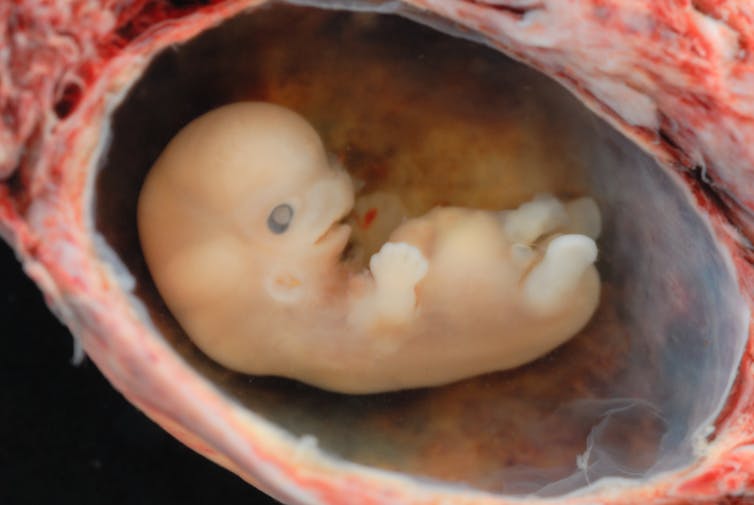

The first of these stages is fertilization in the egg duct, when a zygote is formed with the full human genetic material. But almost every cell in everyone’s body contains that person’s complete DNA sequence. If genetic material alone makes a potential human being, then when we shed skin cells – as we do all the time – we are severing potential human beings.

The second plausible stage is called gastrulation, which happens about two weeks after fertilization. At that point, the embryo loses the ability to form identical twins – or triplets or more. The embryo therefore becomes a biological individual but not necessarily a human individual.